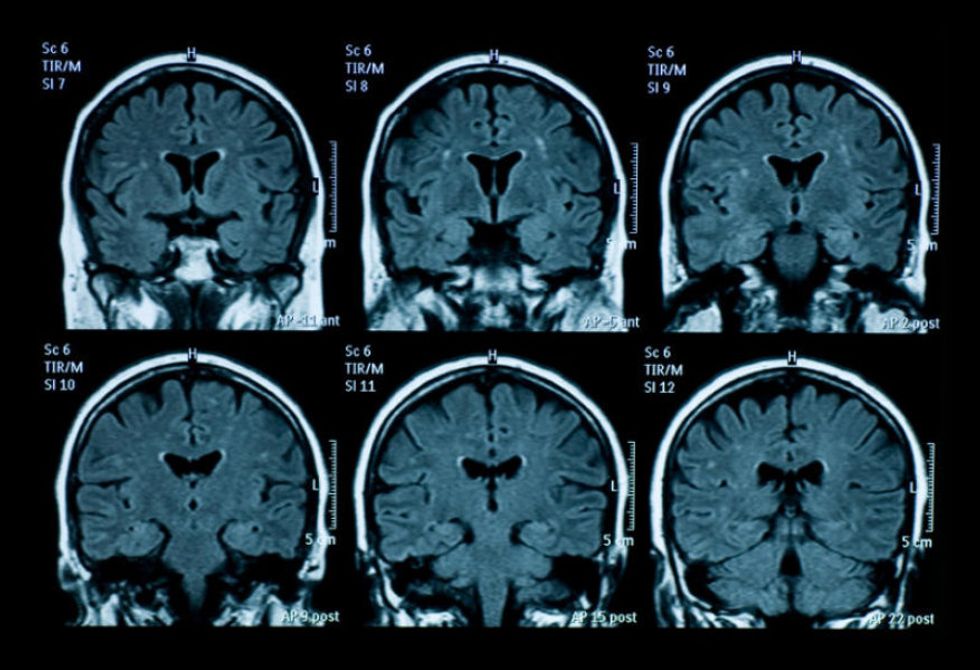

For the best clear answers on why our brain work the way they are, what are some of the more specific neuropsychological tests? The Cognitive Assessment Screening Instrument might be requested for those struggling to concentrate. The Comprehensive Aphasia Test (CAT) scans have been common procedures for both language disorders and head injuries. Most of the neuropsychological tests might be either under review for further research or implausible for the general population. As an adult, they have the choice of receiving tests if it's ever recommended by a doctor. For a child's ongoing treatment, it starts with any test for the earliest exposure possible of special education and family assistance.